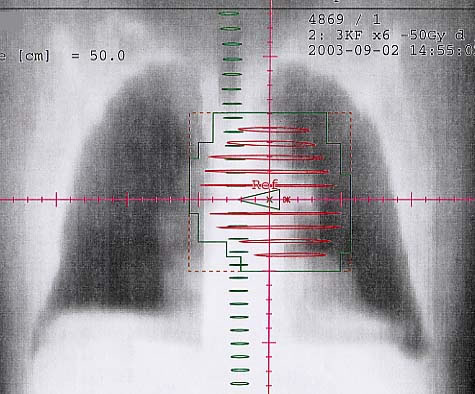

Bronchialkarzinom: Bestrahlungsplan